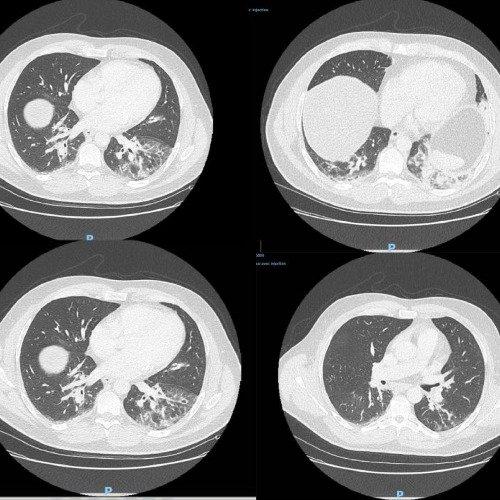

6、文章的图片部分,建议使用更具代表性和高质量的图片,以更好地支持文章内容。